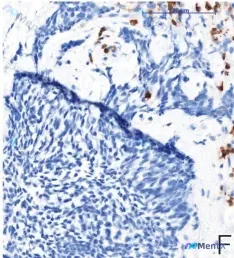

整理了一份病理免疫组化的资料,核心信息如下: - 免疫组化方法:EnVision法,放大倍数×200 - Ki-67增殖指数:明确<5% - 图像补充描述:核阳性信号强、定位准,背景清晰无明显工艺问题;阳性细胞散在分布,无明显热点区聚集;可见肿瘤细胞呈巢状/片状排列,细胞核形态相对规则,缺乏显著异型...